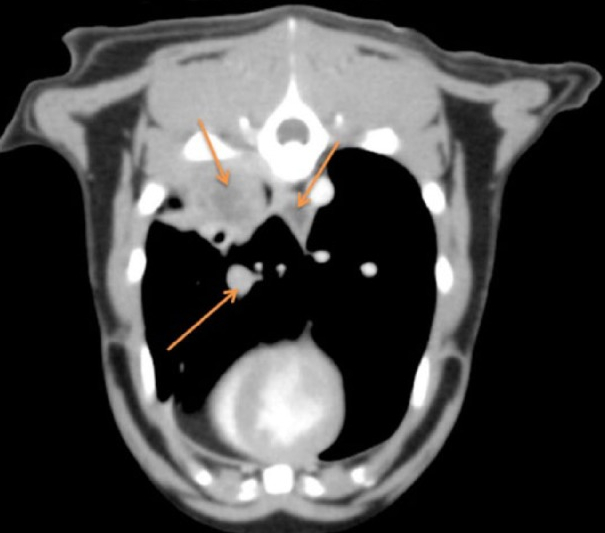

하지만 고양이에서 특이적으로 보이는 증후군인 lung digit syndrome은 이런 상식을 파괴하여

폐 종양이 발가락으로 전이되는 양상으로 관찰되기도 한다.

이 논문에서 소개하는 증례는 너무 극단적으로 상태가 심각한 경우인데

거시 병리적 관점에서도 폐종양이 발가락으로 전이된 전형적인 케이스이다.

이런 사진들도 상당히 진행된 후에 종합검사를 하여 늦게 발견된 케이스들이라 생각보다 심각한편

고양이 발가락폐 증후군은 노령묘에서 발가락에 덩어리짐이 있거나 상처가 생겼을때 반드시 고려해야 하는 항목이라고 기억해야 한다.